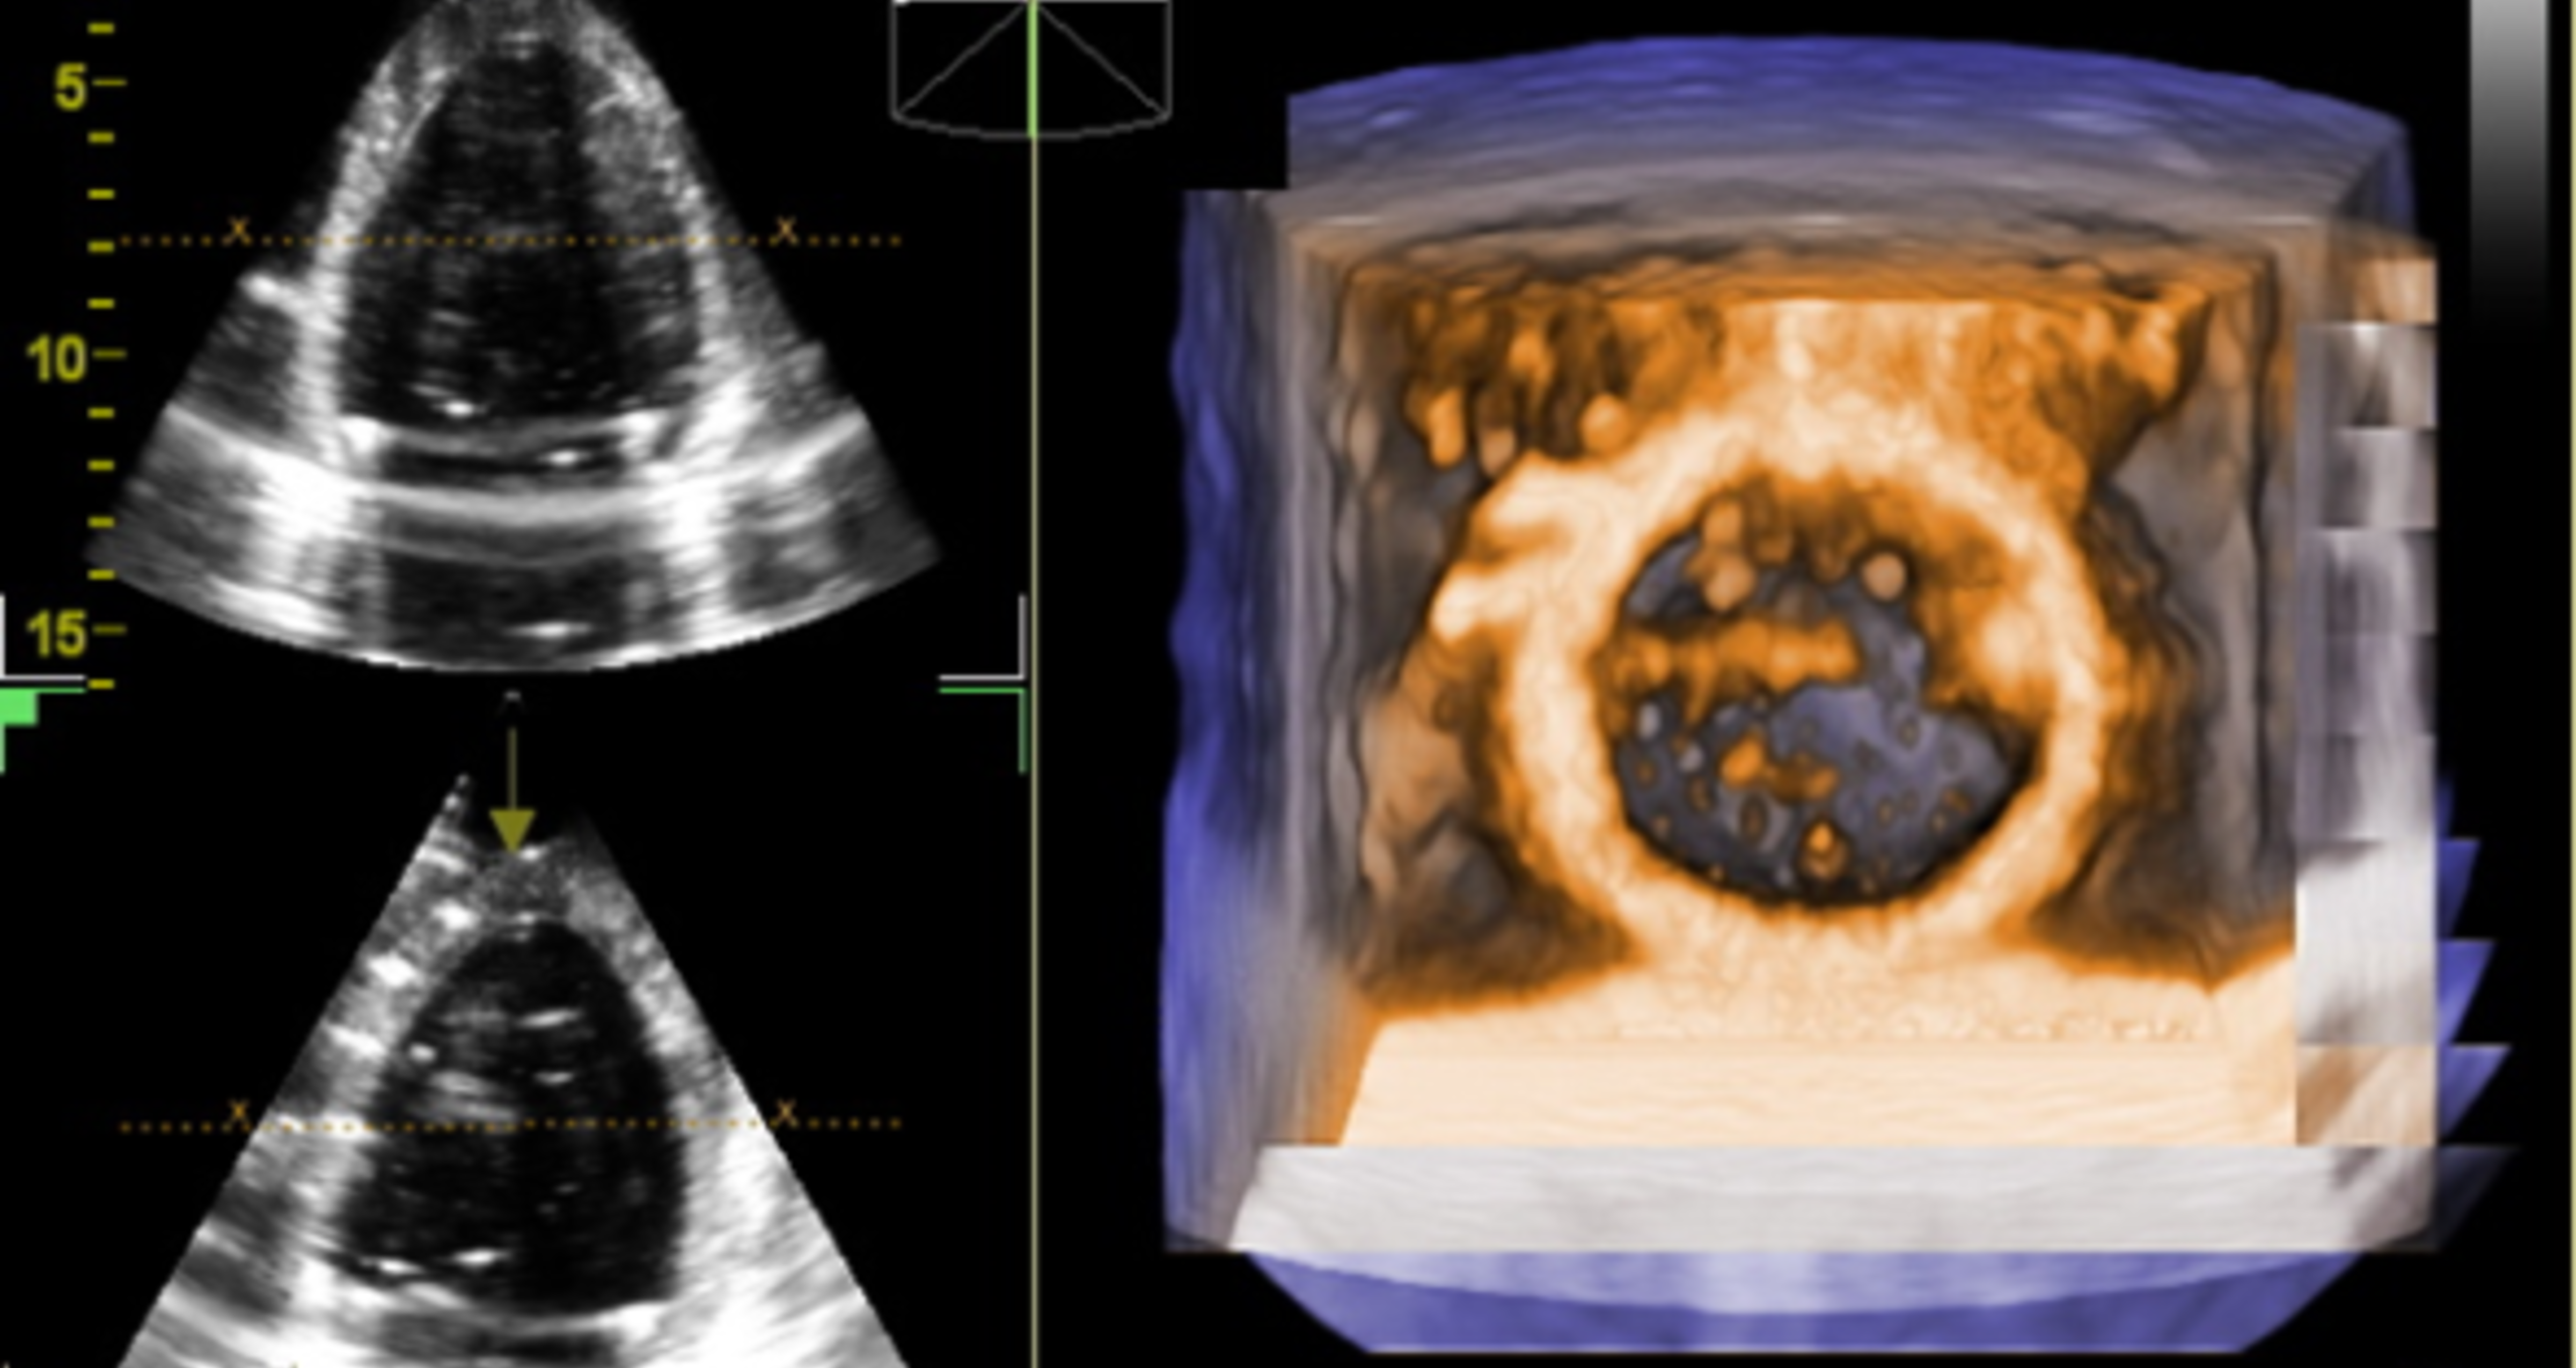

3D opptak

3D visualization

Photo:

Knut Matre, UiB

2. Accuracy of left ventricular 3D strain measurements in the adult heart